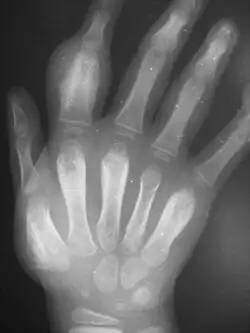

Secondary yaws affects the skin and bones.[12] The most common bone-related problem is periostitis, an inflammation around the bone, which often occurs in the bones of the fingers and the long bones of the lower arms and legs, causing swollen fingers and limbs.[12] This causes pain at night and thickening of the affected bones (periostitis).[2] About 75% of infected children surveyed in Papua New Guinea reported joint pain.[2] Swollen lymph nodes, fever, and malaise are also common.[12]